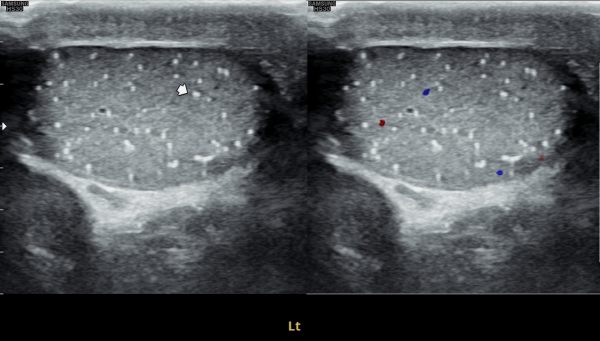

좌측고환의 초음파 검사상 또한 고환의 미석증이 관찰되는 사진입니다.(NIH:24)

On the ultrasound examination of the left testis, multiple tiny echogenic foci without acoustic shadowing are again observed, consistent with testicular microlithiasis.(NIH:24)

주 2회 14주 동안 정관과 사정관, 정낭 그리고 전립선의 표적 치료후 치료되고 있는 좌측 고환 미석증들의 초음파사진입니다.(NIH:13)

This ultrasound image shows improvement of left testicular microlithiasis after targeted treatment of the vas deferens, ejaculatory ducts, seminal vesicles, and prostate.

The treatment was performed twice a week over a period of 14 weeks, and the previously observed tiny calcifications in the testis are gradually improving, suggesting better circulation and recovery of the reproductive tract.(NIH:13)

These images demonstrate that microlithiasis is present bilaterally, not only on the right side but also within the left testis.

Such findings are characterized by the deposition of microscopic calcifications within the seminiferous tubules.

Clinically, testicular microlithiasis is often asymptomatic but may be associated with chronic testicular pain, infertility, or underlying urogenital conditions, and therefore follow-up and further evaluation may be warranted.